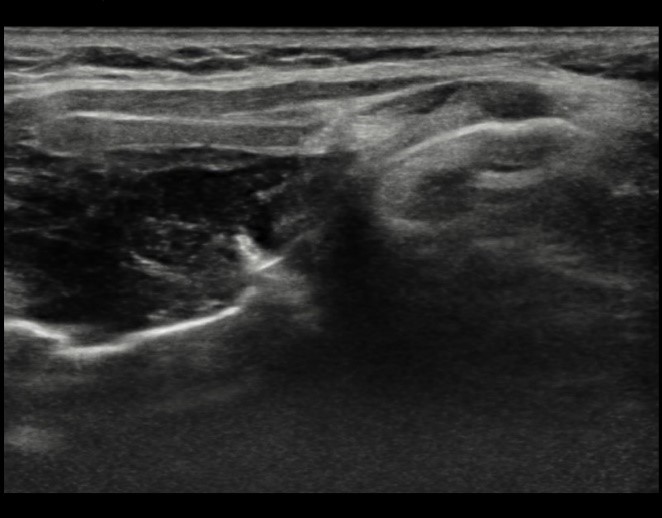

A decision was made to proceed to Ultrasound to see whether (a), any lesion could be seen and (b), whether a biopsy was possible.

The lesion was readily visualized on ultrasound (Figures 4 and 5).

![]() |

Figure 4. Longitudinal image through larynx.

|